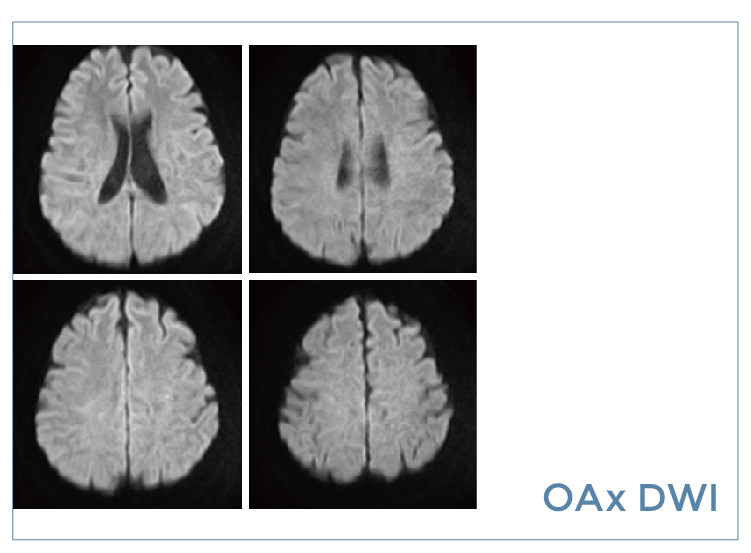

【朗润影像档案】20190823磁共振影像病例结果讨论